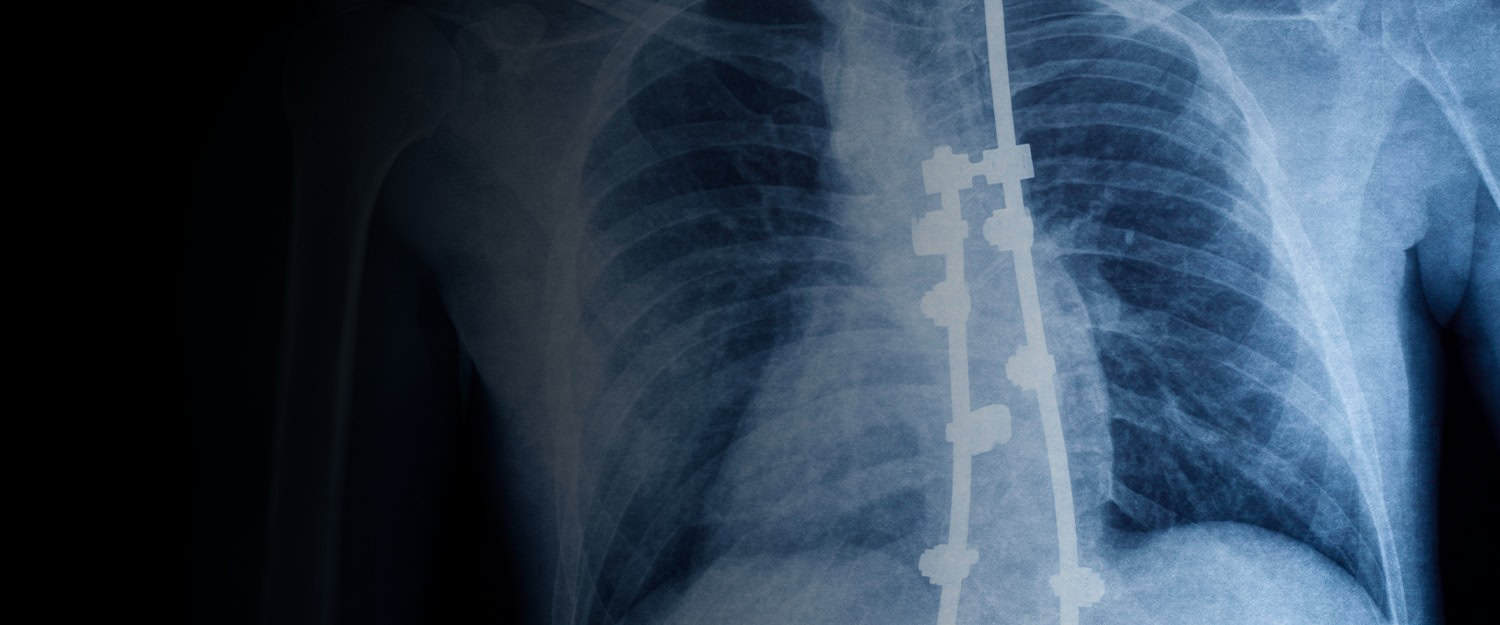

Magnetically Controlled Growing Rods (MCGR) are a modern, growth-friendly surgical option for selected children with progressive scoliosis. MCGR systems use implantable rods that can be gradually lengthened with an external magnetic controller, often reducing the need for multiple surgical lengthening procedures.

Magnetically Controlled Growing Rod (MCGR) systems are implanted along the spine to help guide alignment as a child grows. These rods function as internal supports, assisting in the control of curve progression and maintaining balance.

A key feature of MCGR is the ability to gradually lengthen the rods without the need for surgical incisions. This is accomplished using a magnetic controller placed on the skin above the implant.